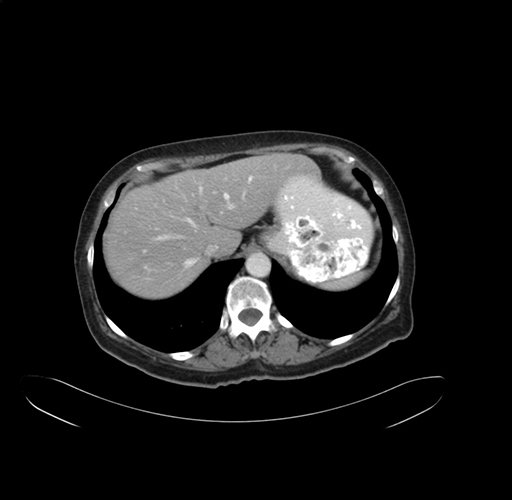

Axial Venous